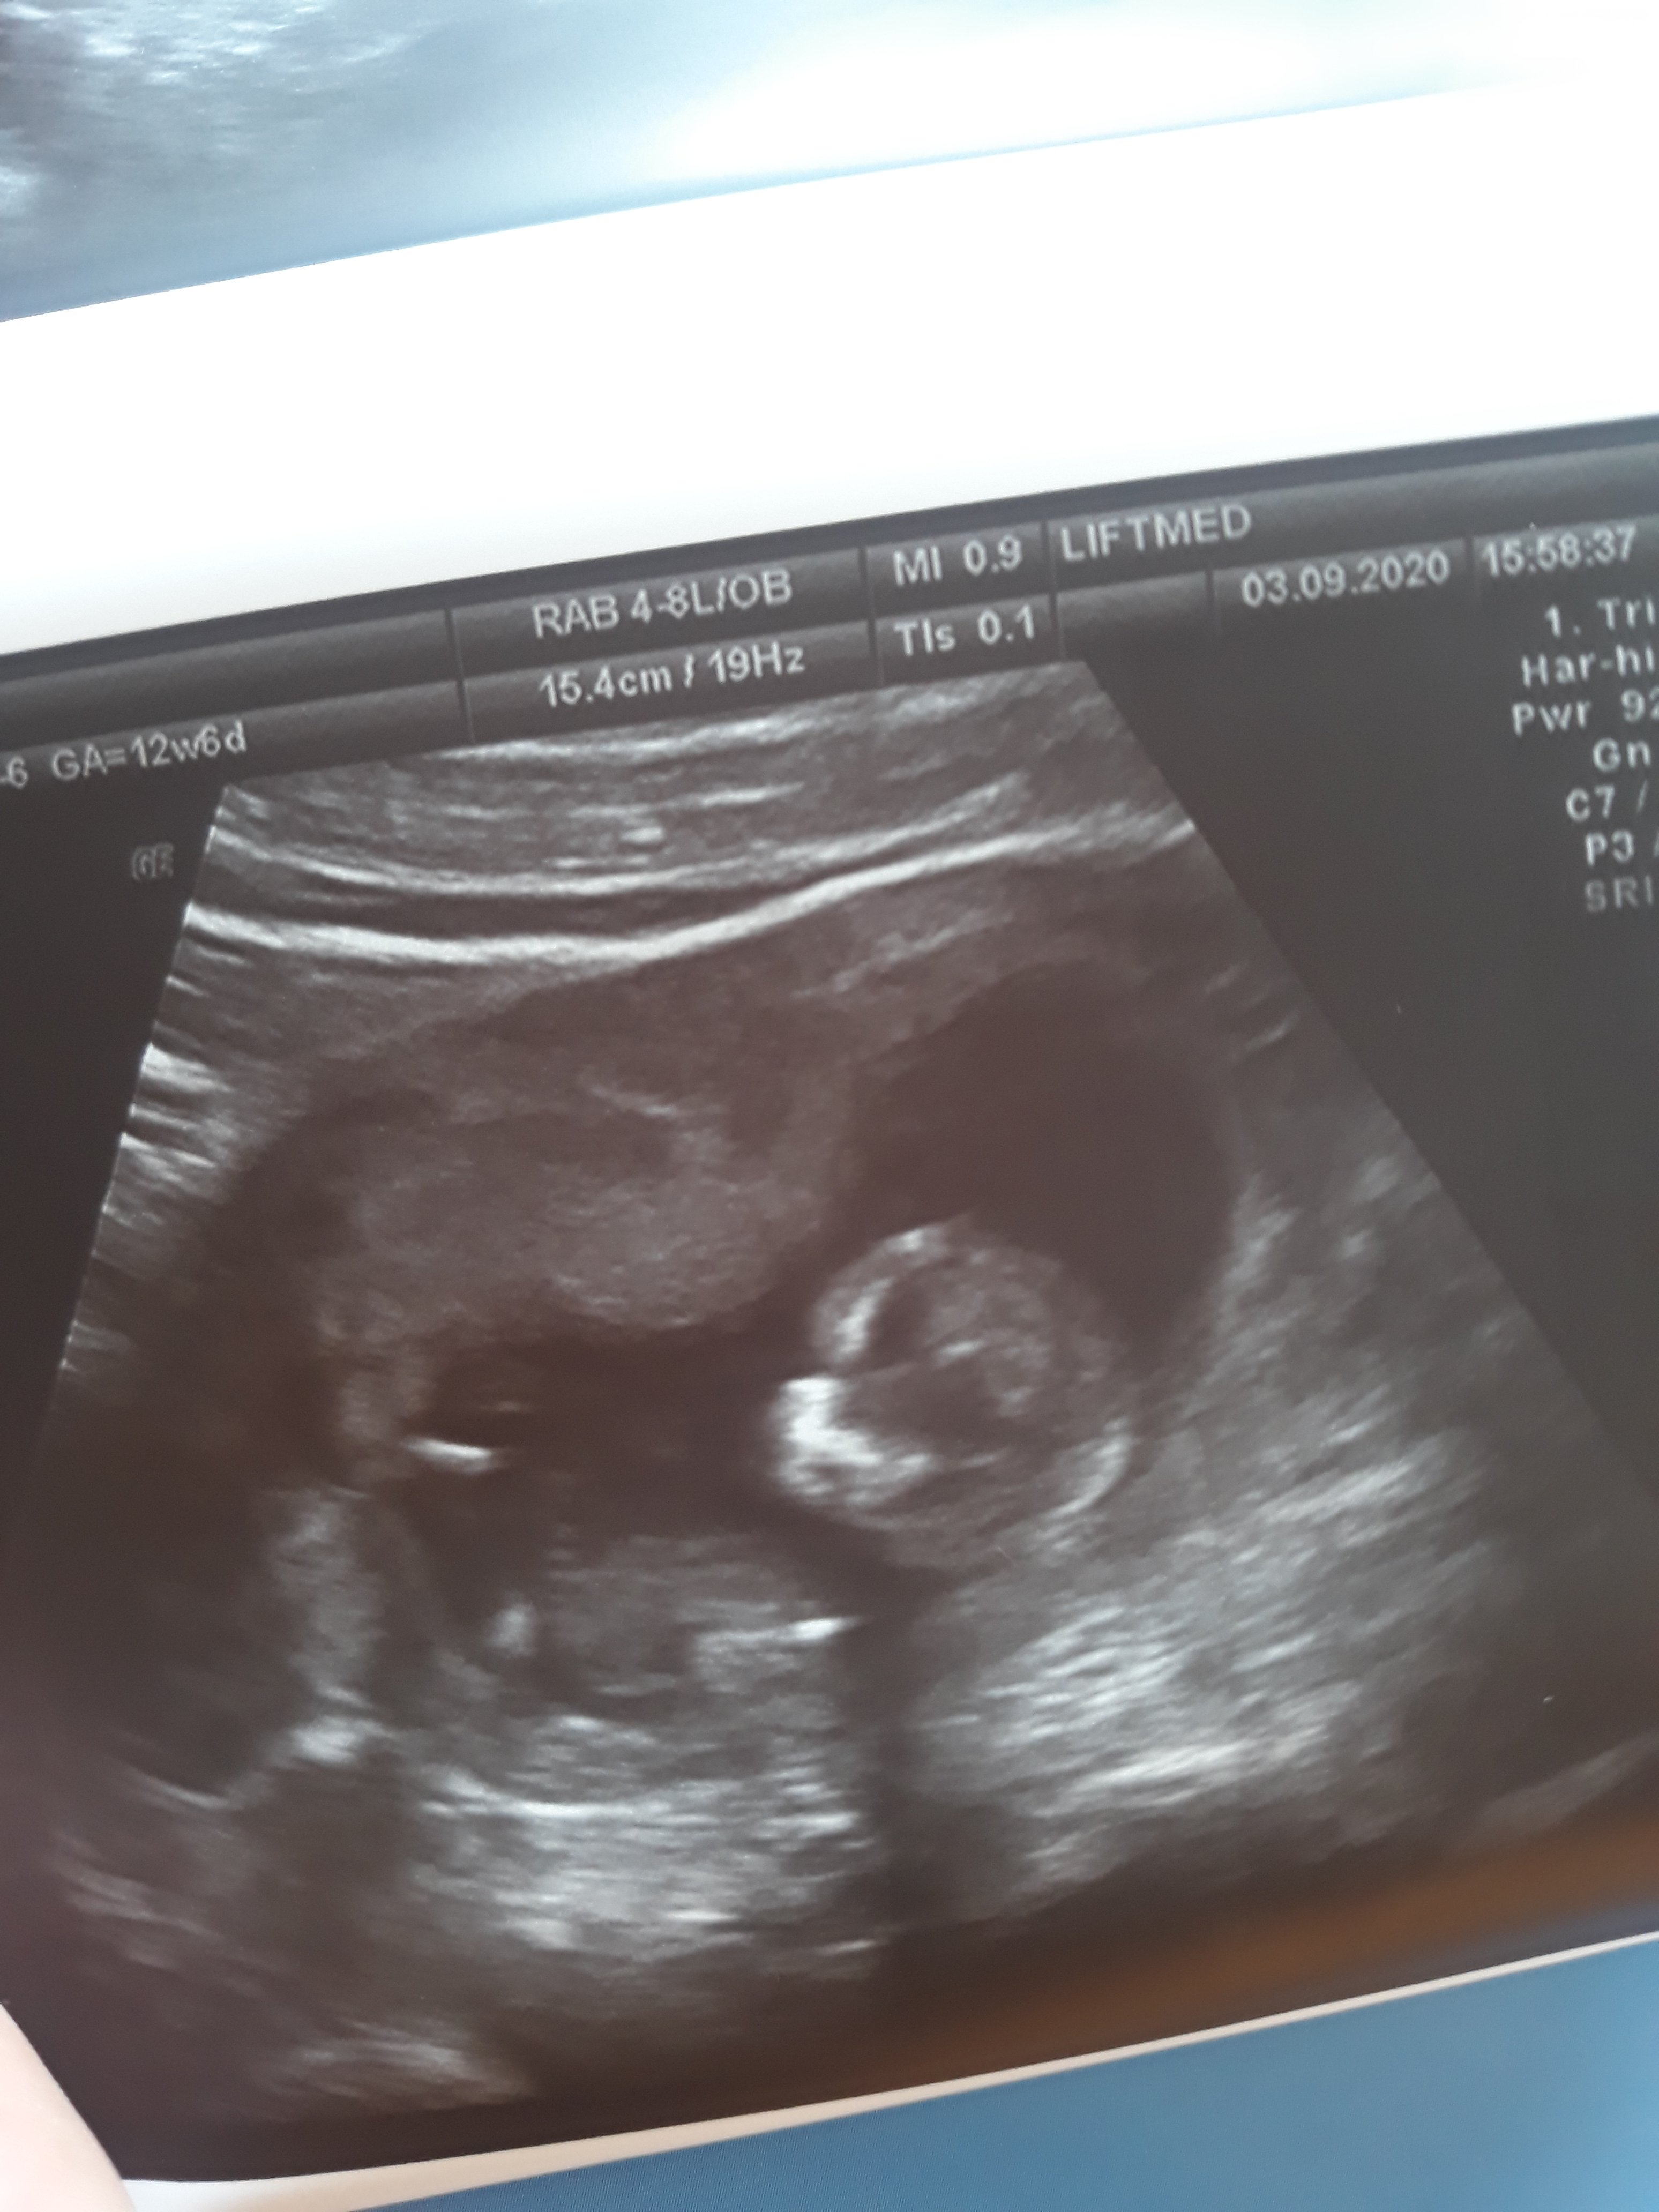

Hej dziewczyny, ja mam maraton po lekarzach w tym tygodniu 🤦‍♀️ takie zalety ciąży. Byłam dzisiaj u swojego lekarza, zrobił mi kolejne można powiedzieć prenatalne, mierzył dokładnie to samo co tamten lekarz wczoraj. Bo oczywiście odwalilam mu lekką histerię że kość udowa jest poniżej normy i co to znaczy :p okazało się że mój gin zrobił bardziej przejrzyste usg niż lekarz z wczoraj i wszystkie parametry policzył na nowo, to mnie trochę uspokoiło. Na dodatek wybił mi dość mocno z głowy robienie nifty czy sanco 🤔 Ale chyba ostateczna decyzja podejmę po wynikach z pappa, na które mimo wszystko patrzę z przymrużeniem oka ;) bo jak wiemy statystyka ma się średnio do rzeczywistości...

A w załączniku pokazuję swojego człowieczka, teraz gdzie widzę co gdzie jest, to jakoś łatwiej mi się z nim utożsamiać :) z tego co dzisiaj lekarz powiedział, jest duża szansa na chłopaka więc trochę tak jak przeczucia mówiły

Załączniki

• 20200903_163744.jpg

20200903_163744.jpg

802,9 KB · Wyświetleń: 93